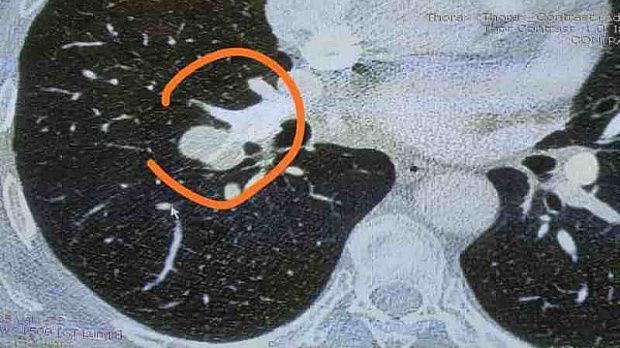

Без всякой постановки провели реальный день с "живыми демонстрациями" очень познавательных клинических случаев. Альвеолярный протеиноз, туберкулёз... непроходимый рубцовый бронхостеноз с бронхоэктазами (молодая пациентка, с 3-мя кардинально разными заключениями из разных учреждений за три недели). Вы, представьте?!

Именно поэтому необходимо общаться на одном языке, не писать фуфло, не только смотреть, но и видеть, клинически мыслить, сопоставлять зоны с КТ, а не ссылаться на старый единственный фибробронхоскоп.